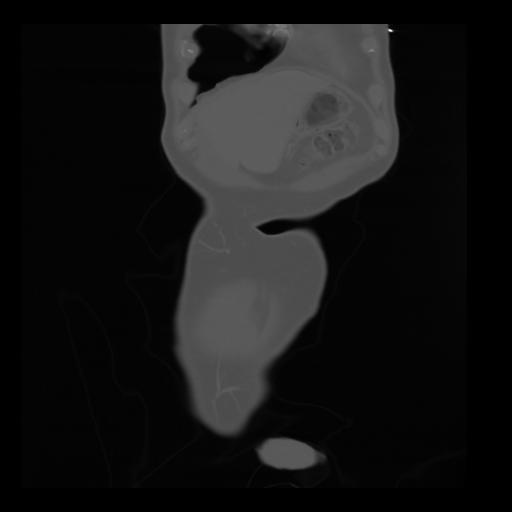

35 CUERPO,CE,Coronal,3.000,CUERPO,Coronal,